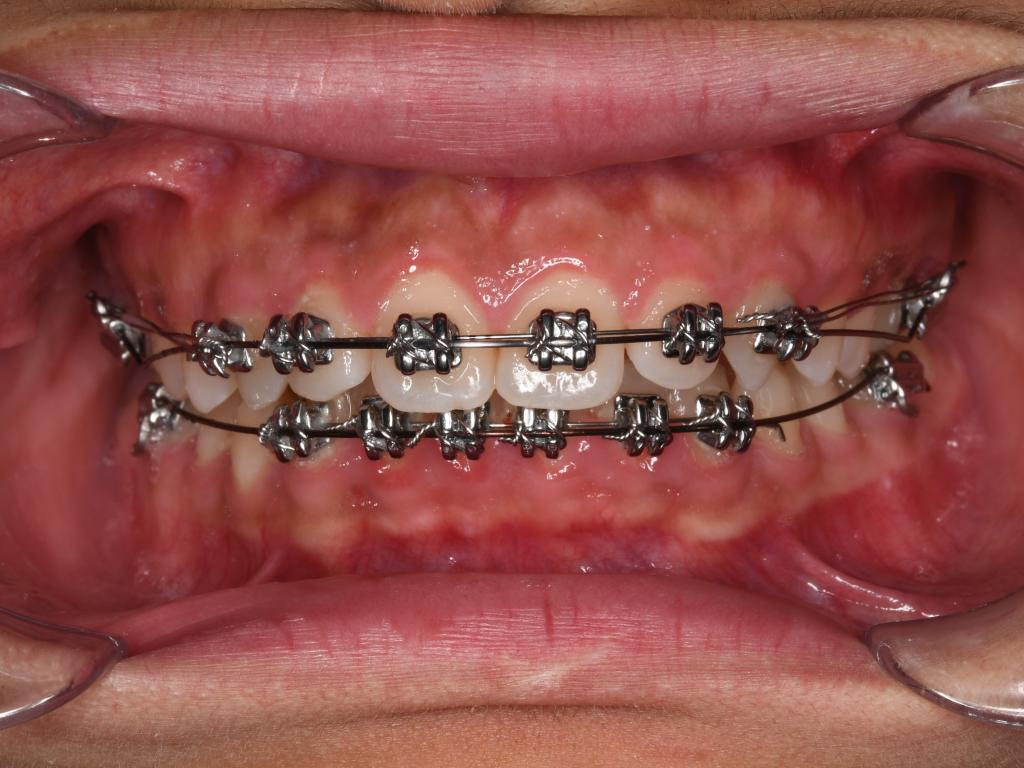

(2) 钢丝扎嘴(结扎丝与弓丝):若为结扎丝扎嘴,可以采用圆钝物体比如筷子、铅笔头等将结扎丝重新压到弓丝的下方,操作过程中力量不要过大,避免托槽松动脱落。若为主弓丝扎嘴,则建议使用粘膜保护蜡或口香糖包裹扎嘴部位(如上图所示)。